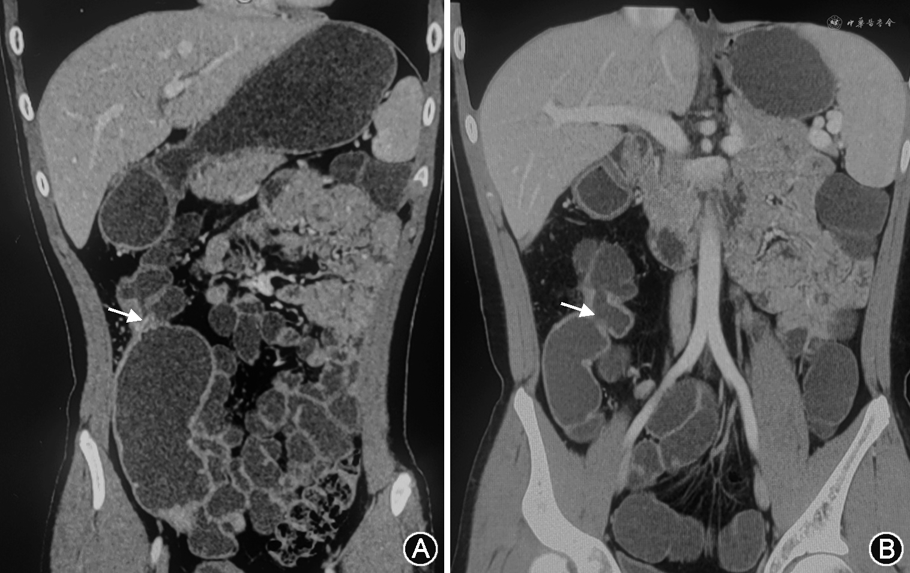

入院后完善血常规、血沉、结核感染T细胞检测、巨细胞病毒-DNA及EB病毒-DNA检查,结果均阴性。大便潜血、抗酿酒酵母抗体阳性,粪便钙卫蛋白(FC)为698 μg/g,C-反应蛋白(CRP)为8.5 mg/g。腹部X线平片见多个小液气平;仿真小肠CT示右下腹吻合口肠壁增厚,强化不均匀,肠腔狭窄,吻合口两侧残留回肠及横结肠肠壁增厚,强化不均匀,肠腔扩张,周围脂肪密度增高,淋巴结稍大。结肠镜示吻合口狭窄合并溃疡。综合考虑诊断:(1)克罗恩病(A1、L2、B3);(2)吻合口狭窄合并溃疡形成;(3)回、结肠部分切除术后。患者诊断明确,除外合并机会性感染,查IFX血药浓度为15.7 mg/L,抗IFX抗体<4 μg/L,肿瘤坏死因子(TNF)-α为101 ng/L,考虑IFX原发失效可能,多学科团队(MDT)讨论后调整治疗为环磷酰胺(CTX)(750 mg/月,静脉滴注)+沙利度胺(75 mg,每晚口服),因患者不能耐受全肠内营养,予以肠内营养粉剂(安素)部分肠内营养,6个月后患者腹痛消失,体重由44 kg增至50 kg,复查CRP结果正常,便潜血(-),FC(-),结肠镜示吻合口狭窄,未见溃疡,予以沙利度胺维持治疗,病情稳定。2019年12月8日患者返院复诊,无腹痛,体重增至58 kg,大便潜血阳性,CRP为14 mg/g,FC为1 376 μg/g;小肠仿真CT示右下腹吻合口肠壁增厚,呈不均匀强化,肠腔狭窄(图1);结肠镜检查示吻合口狭窄伴小溃疡(直径约0.3 cm)(图2A),提示疾病复发可能,但患者无症状,伴体重增加,曾行手术治疗,多种药物治疗无效,要求尽量行内镜下微创治疗,经MDT讨论及医患共同决策后,于内镜室经结肠镜检查至吻合口,经导丝引导通过钳管道予以碘油注射并行造影检查(图2B~2C)除外瘘可能,内镜下于吻合口狭窄处切开(图2D~2E),发现吻合口口侧端活动性溃疡(图2F),调整治疗为醋酸泼尼松片(起始40 mg/d,口服,1个月后开始减量,1周减1片减至20 mg时每2周减1片直至减停)+甲氨蝶呤(MTX)(20 mg/周,肌内注射),期间因吻合口狭窄间断行球囊扩张治疗,半年后复查大便潜血阴性,FC、CRP正常,结肠镜检查示吻合口较前增大,吻合口口侧端溃疡明显好转(图2G~2H),复查小肠仿真CT示吻合口管腔通畅(图1)。患者无不适症状,正常进食,继续MTX单药维持治疗。